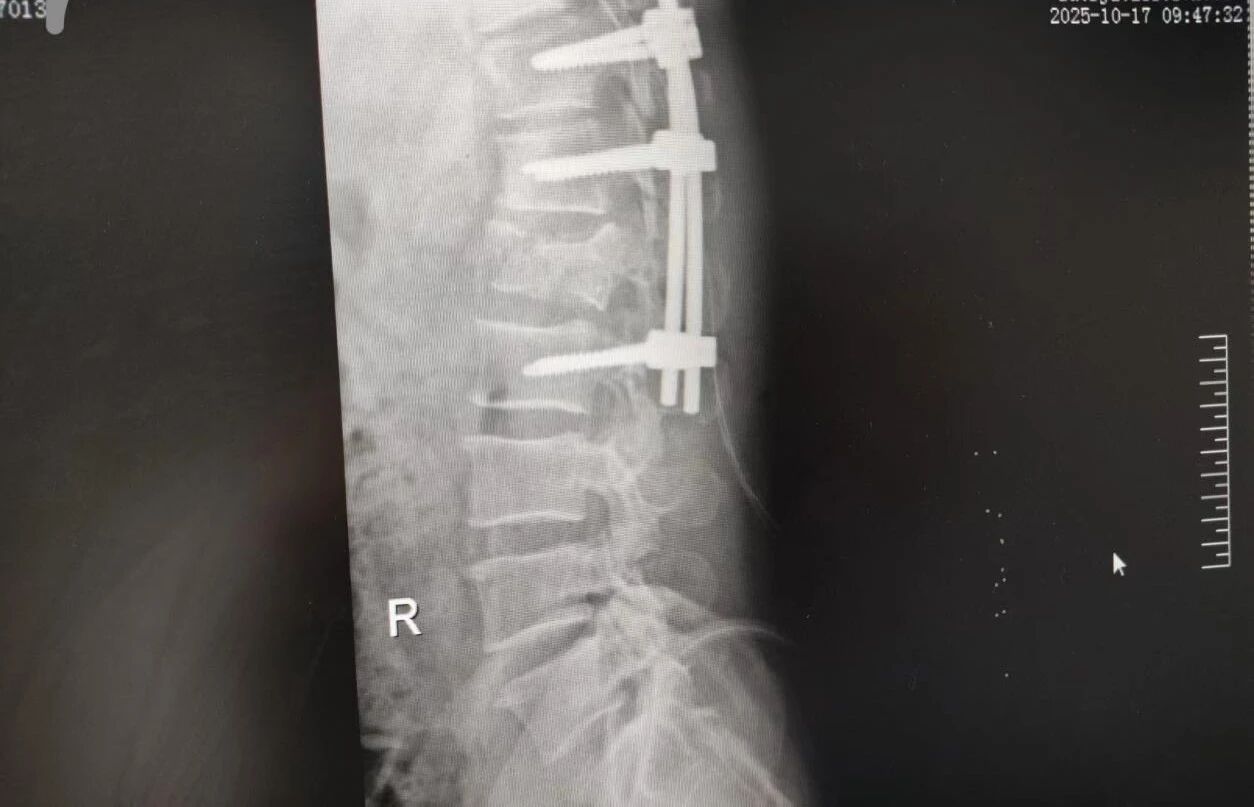

63 歲的王先生(化名)高空作業(yè)時不慎墜落,由漯河市中醫(yī)院急診科緊急接診。入院時,他已生命垂危,初步檢查結果觸目驚心:腰 1 椎爆裂性骨折(脊柱嚴重損傷,隨時面臨永久性癱瘓風險)、多發(fā)肋骨骨折伴血氣胸與肺挫傷(胸腔 “堡壘” 重創(chuàng),呼吸功能幾近崩潰)。任一傷情皆足以致命,多重重創(chuàng)更讓其陷入生死絕境。

針對腰椎傷情,骨科竇志剛醫(yī)生團隊緊急開展腰 1 椎體爆裂性骨折切開復位內固定術 + 椎板切除減壓術。手術室、麻醉科無縫銜接開通綠色通道,手術團隊快速就位,術后患者下肢活動恢復自如。